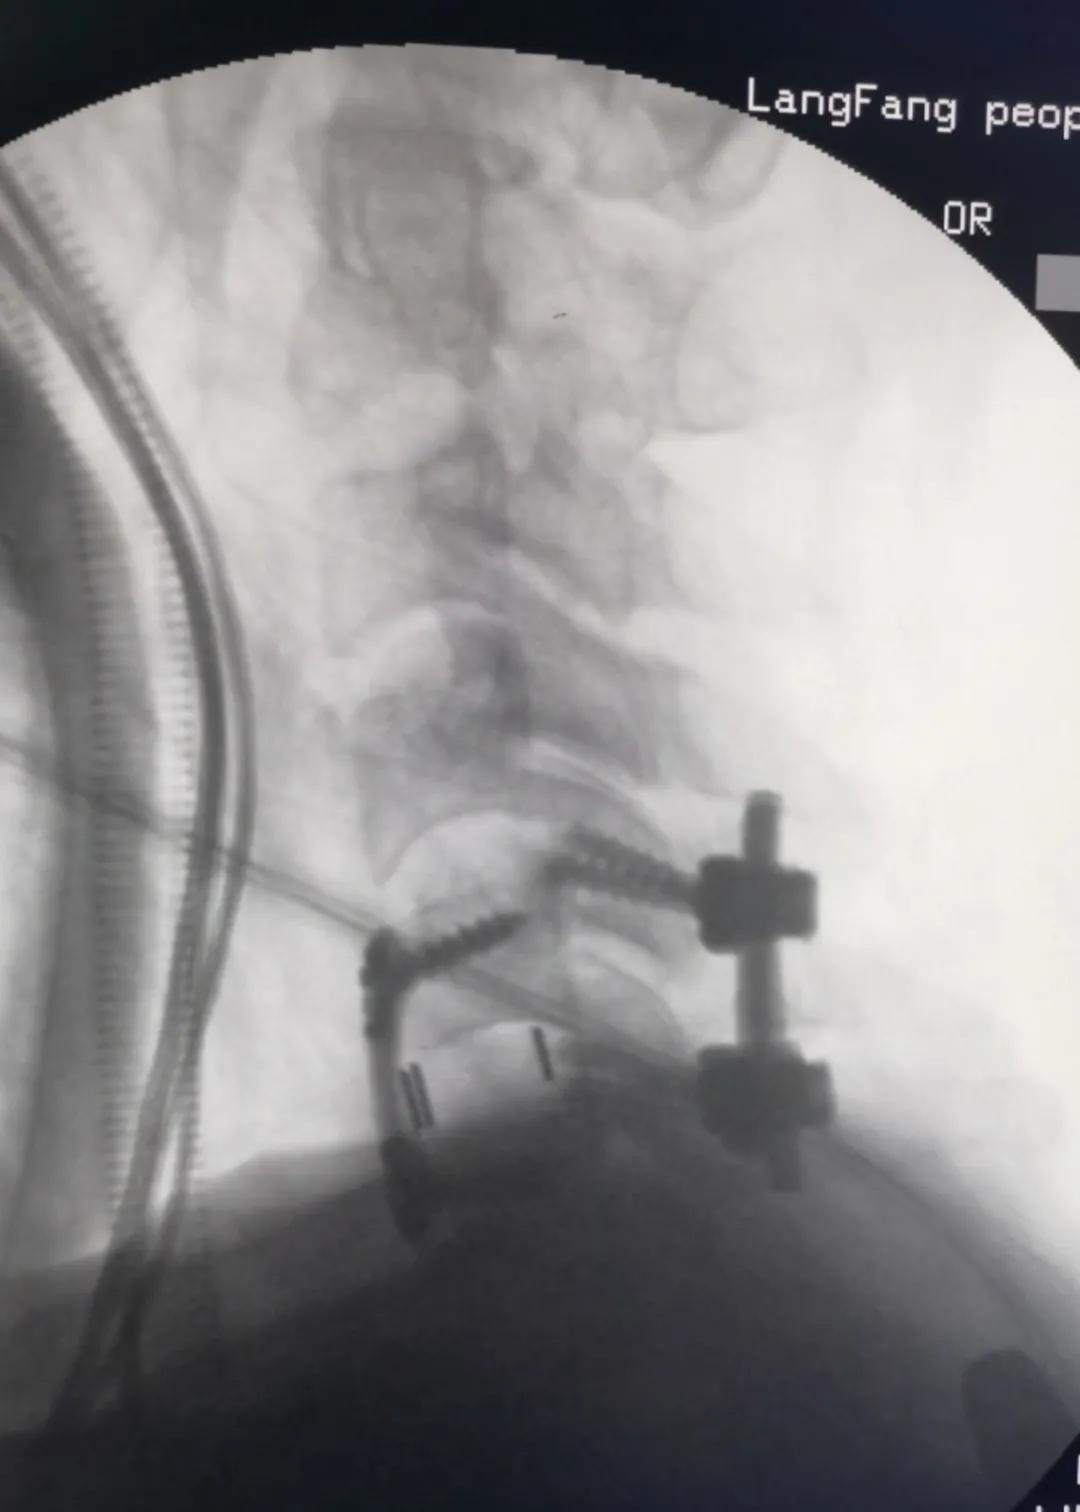

11月3日,某患者因头颈胸部外伤入院。经全面检查,诊断患者为“颈5骨折脱位,双侧关节突交锁、脊髓损伤”。患者入院后,康立星主任带领的骨一科专业团队高度重视,术前经过多次认真讨论,制定了科学周密的治疗方案。在手术麻醉科刘占波主任和马东风医生的通力配合下,康立星主任带领骨科医疗团队为患者施行“一期颈椎前后路联合骨折复位内固定术”。手术过程顺利,未输血,术中颈椎脱位完全复位,固定钢板螺钉位置良好,目前患者恢复良好。